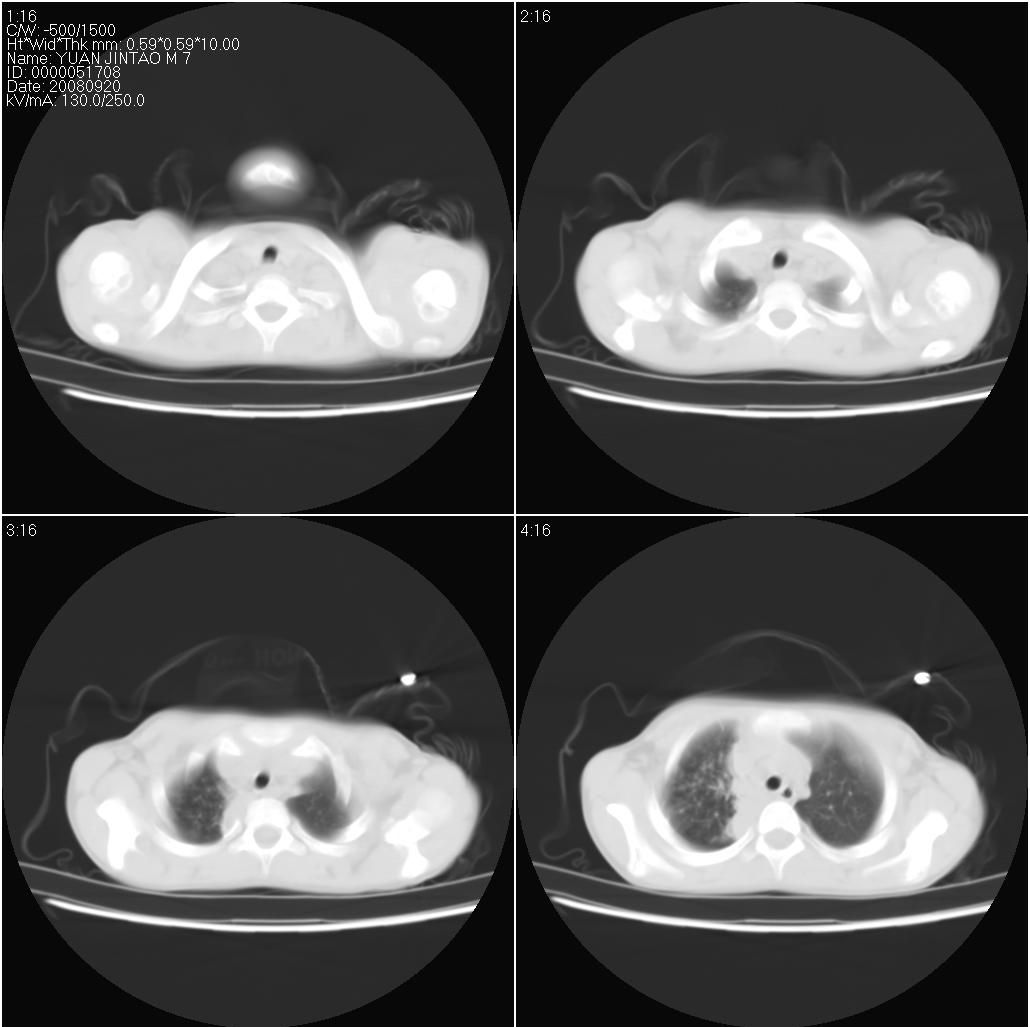

9月20号ct检查情况:

右上肺有班片状条索状高密度影。右肺上叶支气管稍变窄。右前上纵隔有结节状软组织密度影。上腔静脉旁淋巴结肿大。病灶抗炎后扩大。考虑结核可能性大。

右上肺不均匀密度增高,体积变小,水平裂弧状上移,纵隔内有肿大的淋巴结。考虑:

1、右上肺炎(吸收期),纵隔淋巴结肿大压迫右上叶肺膨张不全

2、纵隔淋巴结结核不能排除